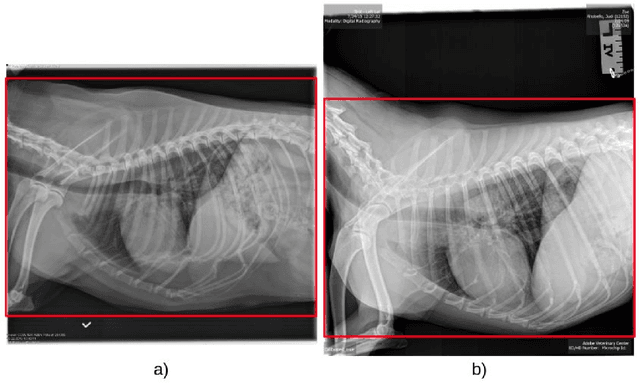

Abstract:Coccidioidomycosis is the most common systemic mycosis in dogs in the southwestern United States. With warming climates, affected areas and number of cases are expected to increase in the coming years, escalating also the chances of transmission to humans. As a result, developing methods for automating the detection of the disease is important, as this will help doctors and veterinarians more easily identify and diagnose positive cases. We apply machine learning models to provide accurate and interpretable predictions of Coccidioidomycosis. We assemble a set of radiographic images and use it to train and test state-of-the-art convolutional neural networks to detect Coccidioidomycosis. These methods are relatively inexpensive to train and very fast at inference time. We demonstrate the successful application of this approach to detect the disease with an Area Under the Curve (AUC) above 0.99 using 10-fold cross validation. We also use the classification model to identify regions of interest and localize the disease in the radiographic images, as illustrated through visual heatmaps. This proof-of-concept study establishes the feasibility of very accurate and rapid automated detection of Valley Fever in radiographic images.